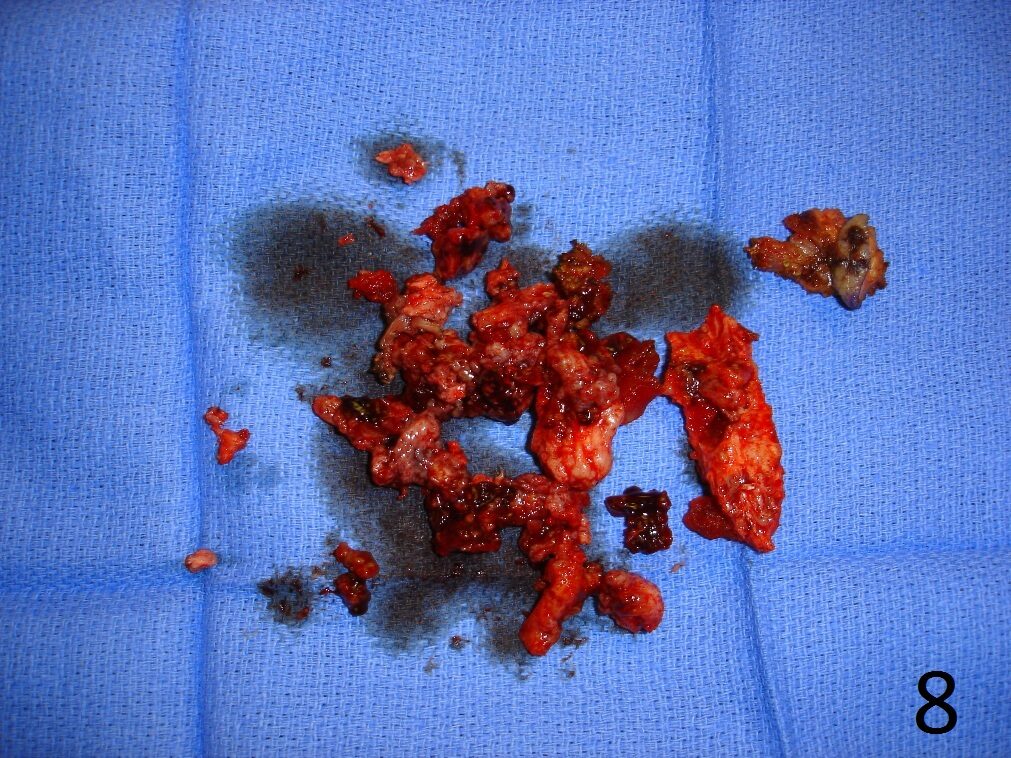

TREATMENT (Fig. 6-12)

Fig. 8

Fig. 6-12: Intraoperative photograph of the lesion (Fig. 6) and steps of the treatment (Fig. 7-12), excision, cryosurgery, gross specimen and cemented internal fixation